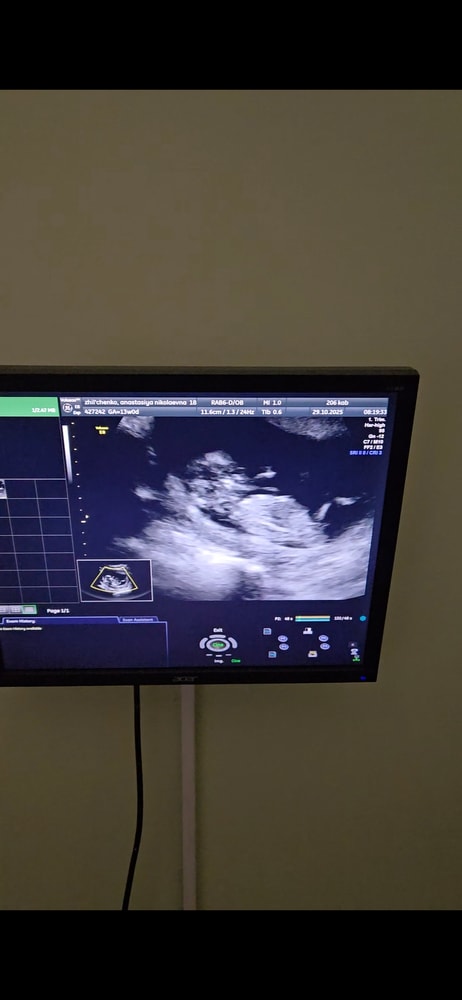

Мальчик/девочка?

Анализы, скринингиХотелось бы послушать знатоков по половым бугоркам 😄 если видно, подскажите) с видео сделала фото

Не понятно - то ли ножка, то ли бугорок. Пока похоже на мальчика.